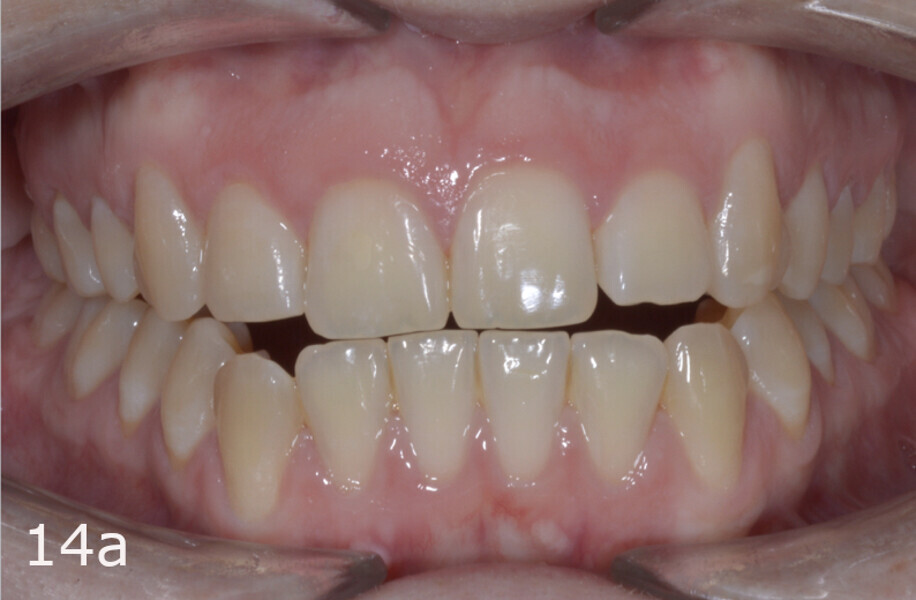

The total treatment time was 15 months. An Angle Class I relationship was established along with adequate anterior and canine guidance, establishing a functional occlusion. This not only ensures optimal masticatory function but also protects the teeth and the temporomandibular joint from excessive force. Maxillary and mandibular fixed retention were installed at the end of the treatment (Figs. 13–19).

This case report has shown that, with a comprehensive diagnosis, proper planning and patient compliance, aligners aided by elastics are an effective and efficient treatment alternative for correcting asymmetric Class III malocclusion. Aligners allow efficient distalisation in patients with anterior open bite or hyper-divergent patterns while minimising the risk of worsening the vertical problems.